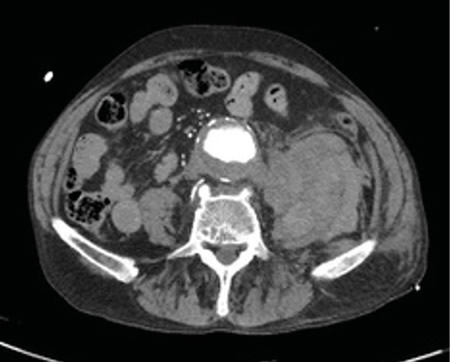

Respecto a las pruebas complementarias, en la analítica sanguínea, se halla una PCR de 39,1 mg/l, leucocitosis de 21.300/mm3, con 88 % de neutrófilos, y una hemoglobina de 10,5 g/dl. En la radiografía pélvica no se evidencian hallazgos patológicos. Debido a la hipotensión, se decide realizar un TC abdominal (Figuras 1 y 2), en el que se objetiva un aneurisma de aorta infrarrenal roto, con diámetro de 50 x 52 x 48 milímetros, a 50 mm de arteria renal derecha y a 65 mm de arteria renal izquierda, craneal a la bifurcación ilíaca. Asimismo, se aprecia un hematoma retroperitoneal en contexto de sangrado en parte posterior de la aorta, que infiltra el músculo psoas ilíaco izquierdo, justificando la clínica de coxalgia con irradiación izquierda. Se contacta con cirugía vascular, interviniéndose de forma urgente, con buena evolución posterior.

Fig. 2. TC transversal de aneurisma de aorta abdominal.